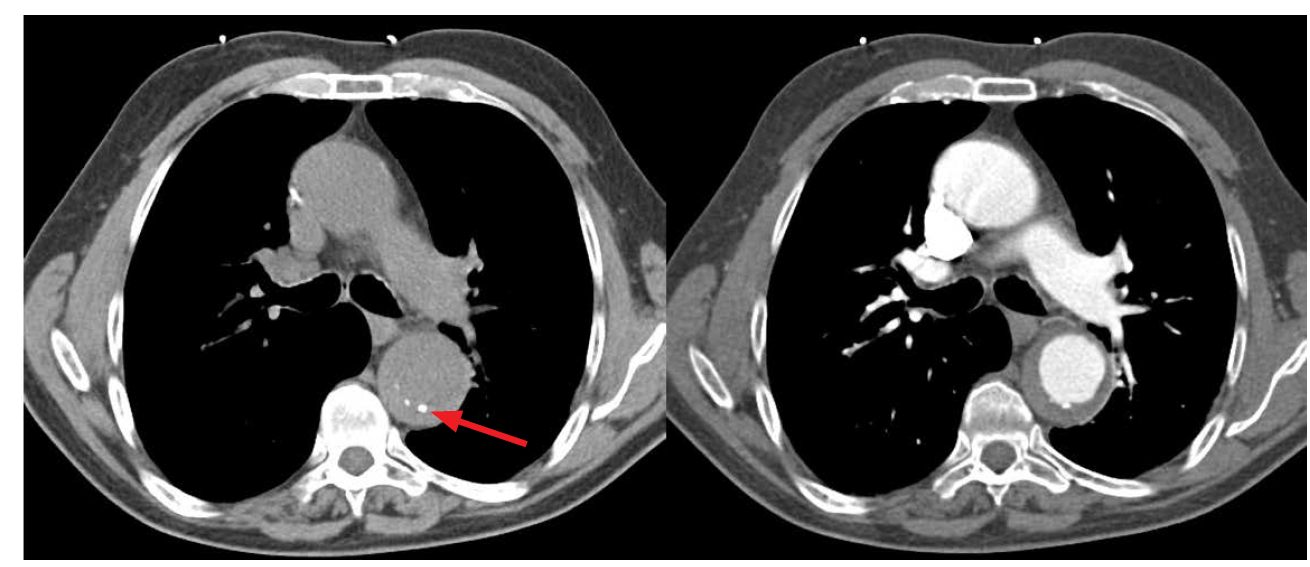

What is this?

IMH